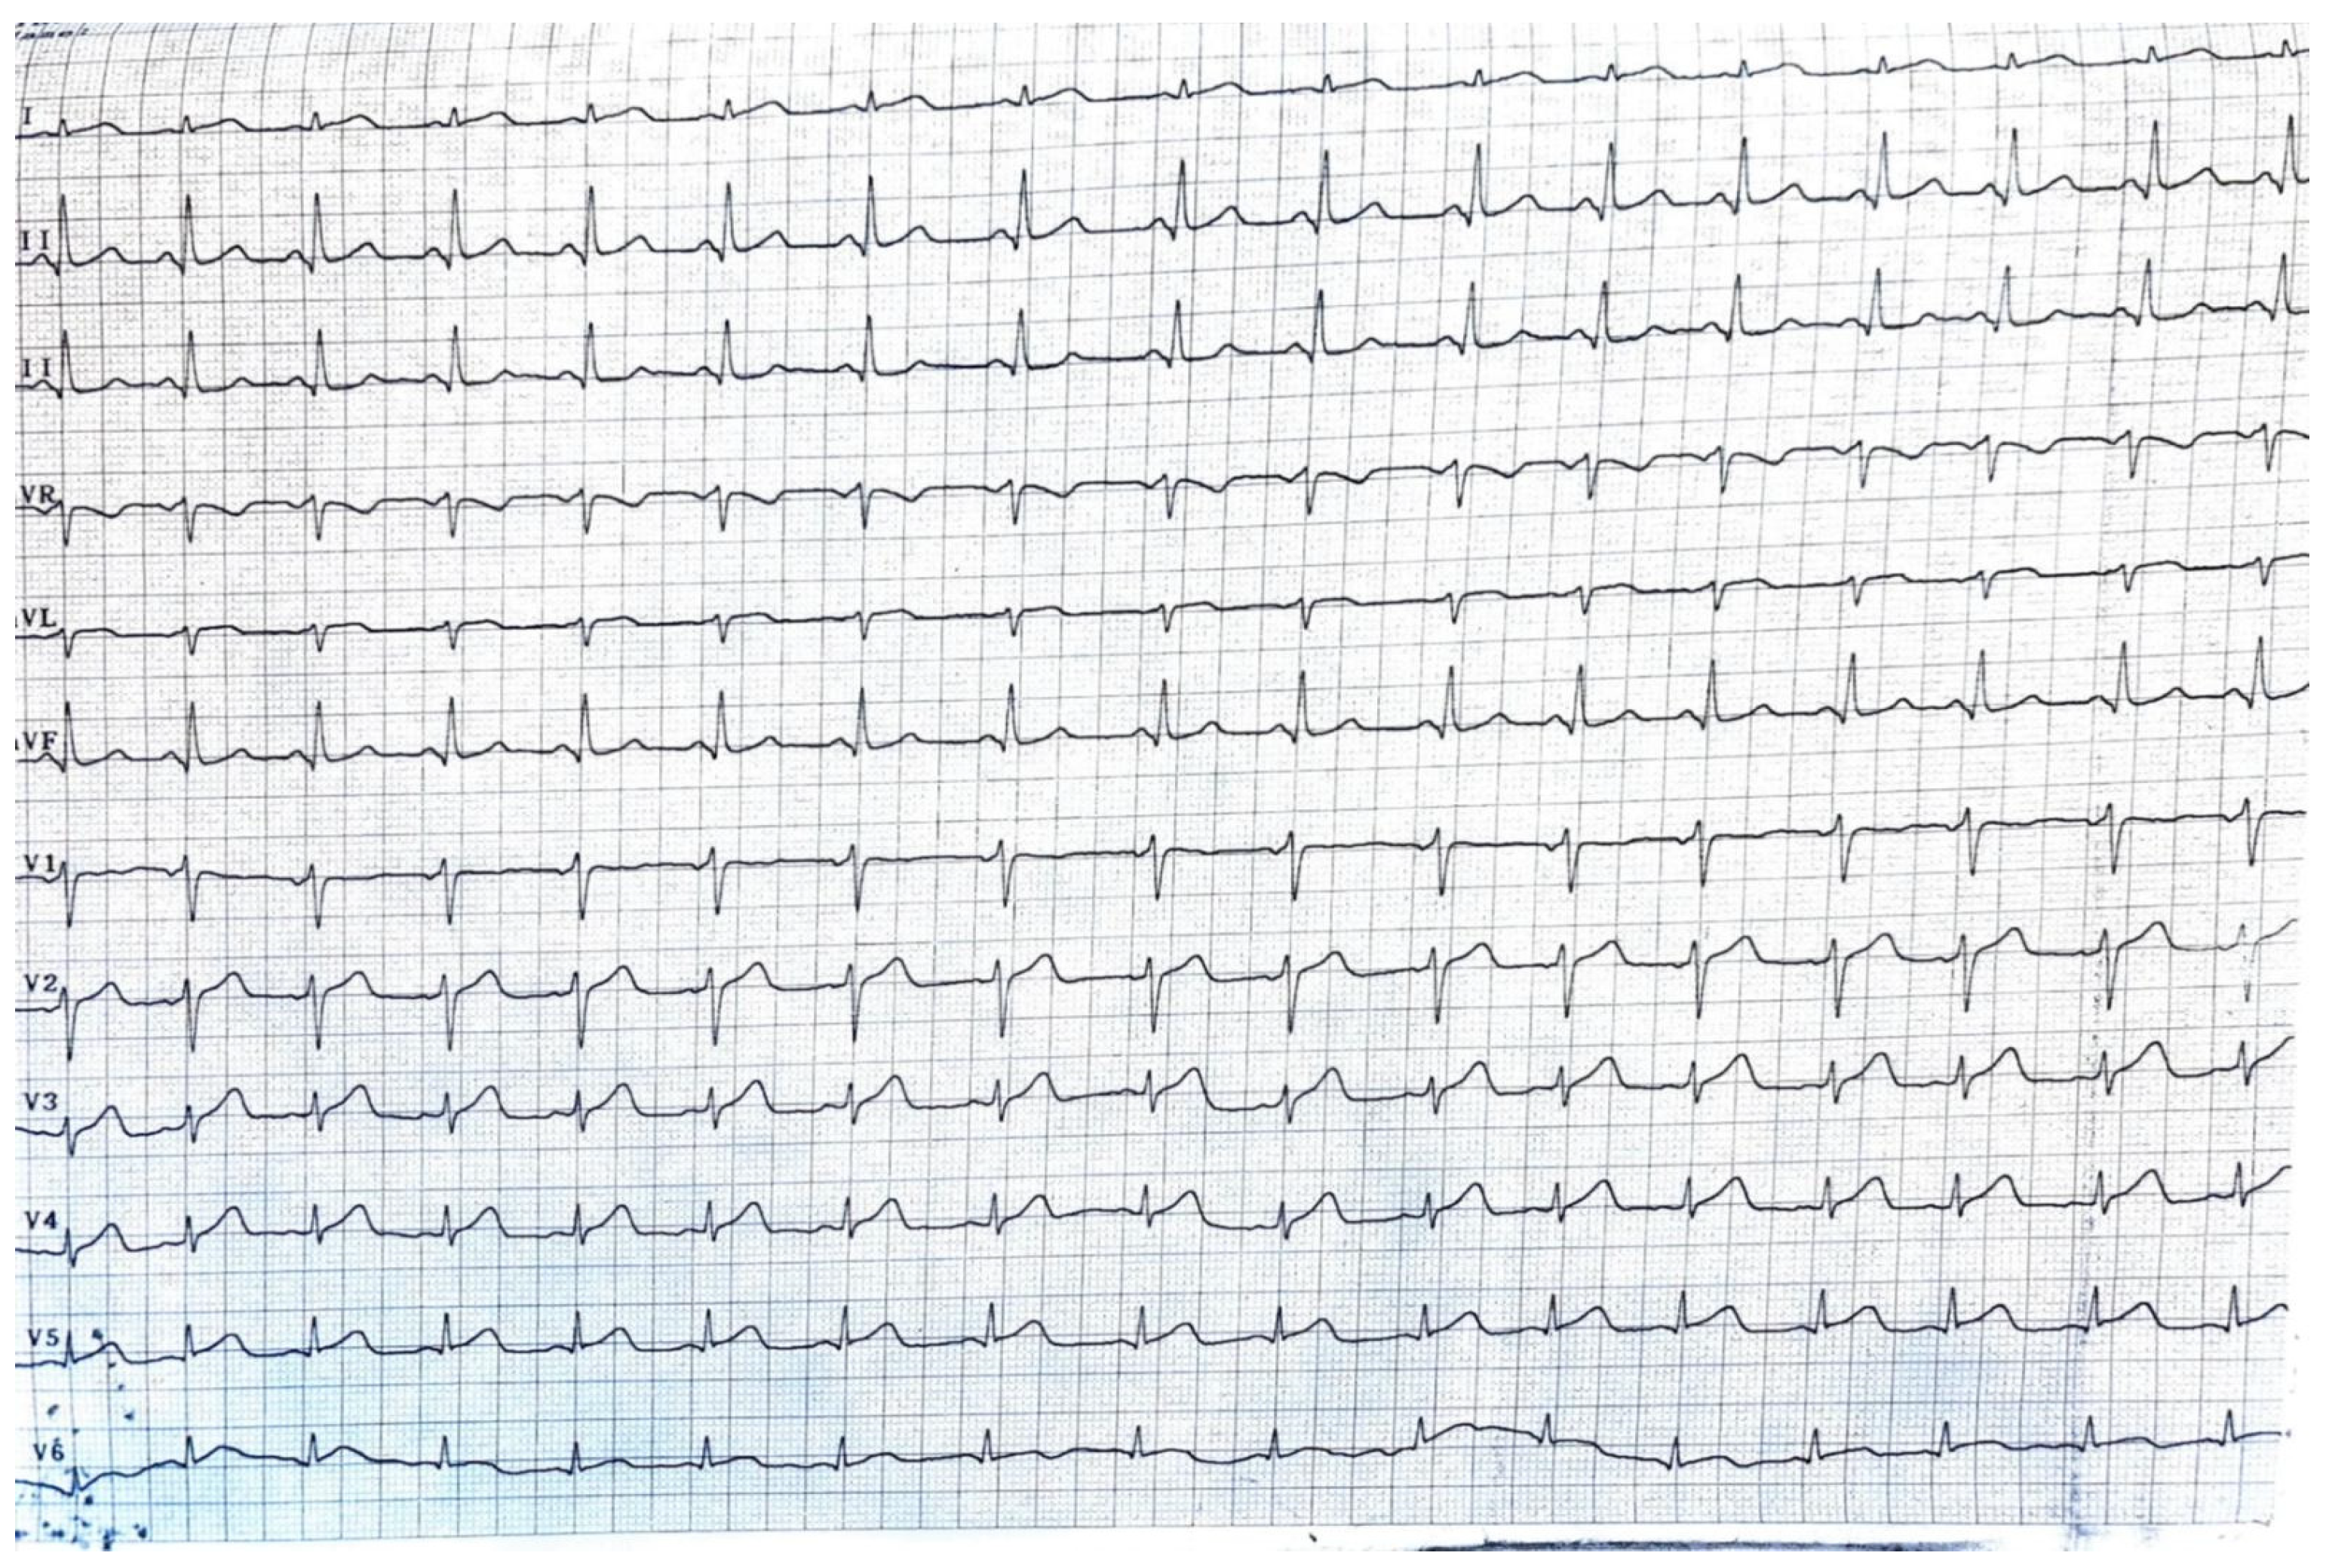

The peritoneal cancer index (PCI) [6] in this case was 14, suggesting a moderate degree of peritoneal surface involvement by the peritoneal carcinomatosis. The peritoneal cancer index (PCI) is a numerical score used during CRS to quantify the extent of disease in different regions of the abdomen and pelvis. With a PCI of 14, there is a moderate volume of disease present in various regions. The significance of this score depends on several factors, including the specific locations of tumor involvement, the type of cancer, and the overall health of the patient [7]. The cardiological evaluation prior to surgery revealed no significant cardiac comorbidities with no ventricular dilatation and an ejection fraction (EF) of 65%. No coronarography was requested, as the patient had no history of past cardiac events (Figure 3).

Figure 3.

The ECG of the patient at admission, showing no signs of modifications.